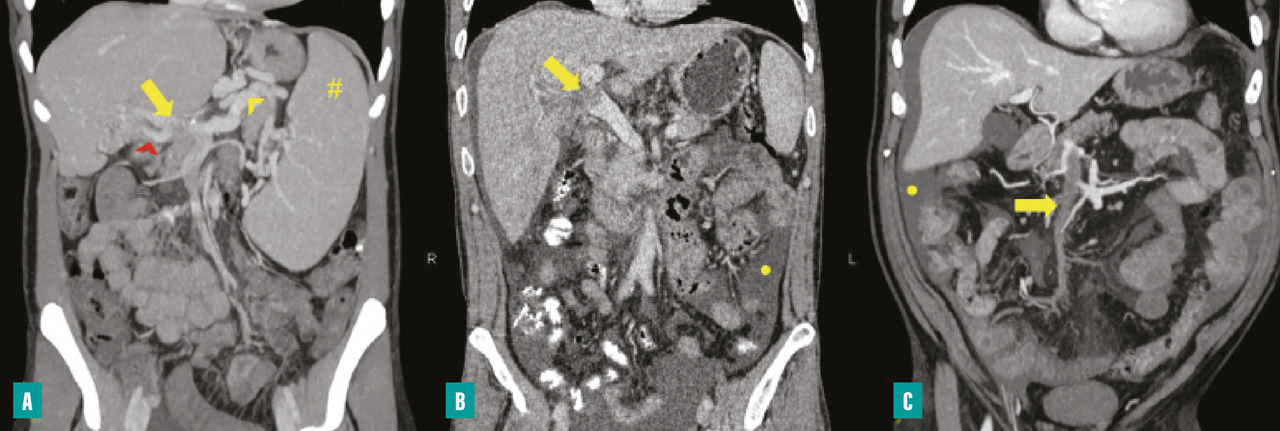

Le diagnostic de TVP récente repose sur l’imagerie. Elle doit être réalisée chez tout patient qui en présente une suspicion clinique. L’échographie-Doppler est généralement l’examen de première intention  ; elle permet la visualisation directe du thrombus dans la veine porte et l’absence de flux au Doppler en cas de TVP complète (sensibilité de 88 à 98  %, spécificité de 80 à 100  %). Elle doit être complétée systématiquement par un scanner (ou une imagerie par résonance magnétique [IRM]) abdominal avec injection de produit de contraste, et aux quatre temps d’acquisition (sans injection, phase artérielle, portale et tardive), si cette imagerie n’a pas été réalisée d’emblée. Le scanner permet de confirmer le diagnostic de TVP, de déterminer le degré d’extension aux veines spléniques et mésentériques, de rechercher un facteur local et des signes d’ischémie mésentérique. De plus, il permet d’identifier des signes d’hépatopathie chronique sous-jacente (dysmorphie hépatique, signes d’hypertension portale) [fig. 2].

Une ischémie mésentérique est recherchée systématiquement sur le scanner abdominal aux quatre temps (sans injection, temps artériel, portal et tardif) et est confirmée par la constatation de signes de souffrance intestinale associés à la TVP tels qu’un épaississement de la paroi intestinale et/ou une diminution de rehaussement des anses après injection de produit de de contraste. La mise en évidence d’une absence de rehaussement pariétal, d’une dilatation intestinale supérieure à 25 mm ou encore d’une pneumatose intestinale voire aéroportie (présence de gaz dans la lumière de la veine porte) sont des signes de gravité évoquant une nécrose intestinale et indiquant un traitement chirurgical.